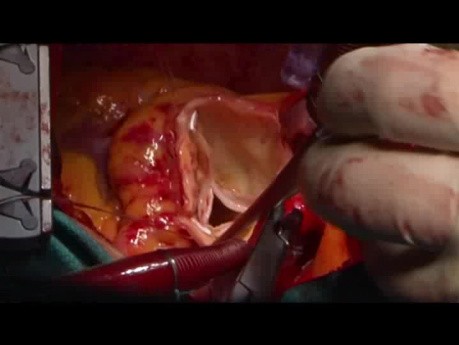

Rekonstrukcja opuszki i aorty wstępującej - cały...

Materiał przedstawia zabieg rekonstrukcji opuszki i aorty wstępującej. Zabieg ten zalecany jest wśród pacjentów kwalifikowanych do zabiegu operacyjnego z powodu tętniaka aorty wstępującej i z niedomykalnością...

Rekonstrukcja opuszki i aorty wstępującej

Film prezentuje zabieg rekonstrukcji opuszki i aorty wstępującej. Zabieg ten zaleca się pacjentom kwalifikowanym do zabiegu operacyjnego z powodu tętniaka aorty wstępującej i z niedomykalnością zastawki...